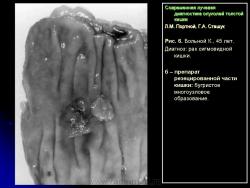

В 1961 г. Wellin предложил методику рентгенологического исследования толстой кишки, названную автором одномоментным двойным контрастированием толстой кишки (ОДКТК). Основное отличие ее от классической ирригоскопии состоит в том, что для исследования толстой кишки используется значительно меньшее количество бариевой взвеси и сразу же, по мере ее введения в дистальные отделы кишки, дальнейшее продвижение осуществляется специальным одноразовым устройством с помощью воздуха, вводимого под контролем рентгенотелевидения с учетом клинических особенностей пациента. Опыт многих исследователей и наш личный опыт указывают, что такие предосторожности при исследовании обусловлены не возможностью осложнений, а тем, что нередко быстрое контрастирование кишки может вызвать спазм отдельных ее участков и тем самым уменьшить его эффективность. Как правило, для исследования всех отделов толстой кишки, так же как и приирригоскопии, применяется стандартизованная методика с использованием тех же пяти проекций. Фиксация изображения осуществляется на рентгеновскую пленку средних размеров 18 х 24, 24 х 30 см. Основными достоинствами ОДКТК следует считать его высокую диагностическую эффективность, методическую простоту и возможность использования при скрининговых обследованиях групп риска по раку толстой кишки. В ОДКТК удачно сочетаются фазы “тугого” наполнения и двойного контрастирования – основные элементы, позволяющие фиксировать внутристеночную инфильтрацию кишки в ее начальных проявлениях с помощью определения состояния контура кишки и толщины стенки. Двойное контрастирование позволяет получить исчерпывающую информацию о слизистой кишки, которая при отсутствии в ней изменений (небольших полиповидных образований, изъязвлений и др.) должна быть полностью разглажена и лишена складчатости (рис. 1).

В 1961 г. Wellin предложил методику рентгенологического исследования толстой кишки, названную автором одномоментным двойным контрастированием толстой кишки (ОДКТК). Основное отличие ее от классической ирригоскопии состоит в том, что для исследования толстой кишки используется значительно меньшее количество бариевой взвеси и сразу же, по мере ее введения в дистальные отделы кишки, дальнейшее продвижение осуществляется специальным одноразовым устройством с помощью воздуха, вводимого под контролем рентгенотелевидения с учетом клинических особенностей пациента. Опыт многих исследователей и наш личный опыт указывают, что такие предосторожности при исследовании обусловлены не возможностью осложнений, а тем, что нередко быстрое контрастирование кишки может вызвать спазм отдельных ее участков и тем самым уменьшить его эффективность. Как правило, для исследования всех отделов толстой кишки, так же как и приирригоскопии, применяется стандартизованная методика с использованием тех же пяти проекций. Фиксация изображения осуществляется на рентгеновскую пленку средних размеров 18 х 24, 24 х 30 см. Основными достоинствами ОДКТК следует считать его высокую диагностическую эффективность, методическую простоту и возможность использования при скрининговых обследованиях групп риска по раку толстой кишки. В ОДКТК удачно сочетаются фазы “тугого” наполнения и двойного контрастирования – основные элементы, позволяющие фиксировать внутристеночную инфильтрацию кишки в ее начальных проявлениях с помощью определения состояния контура кишки и толщины стенки. Двойное контрастирование позволяет получить исчерпывающую информацию о слизистой кишки, которая при отсутствии в ней изменений (небольших полиповидных образований, изъязвлений и др.) должна быть полностью разглажена и лишена складчатости (рис. 1).

В 1961 г. Wellin предложил методику рентгенологического исследования толстой кишки, названную автором одномоментным двойным контрастированием толстой кишки (ОДКТК). Основное отличие ее от классической ирригоскопии состоит в том, что для исследования толстой кишки используется значительно меньшее количество бариевой взвеси и сразу же, по мере ее введения в дистальные отделы кишки, дальнейшее продвижение осуществляется специальным одноразовым устройством с помощью воздуха, вводимого под контролем рентгенотелевидения с учетом клинических особенностей пациента. Опыт многих исследователей и наш личный опыт указывают, что такие предосторожности при исследовании обусловлены не возможностью осложнений, а тем, что нередко быстрое контрастирование кишки может вызвать спазм отдельных ее участков и тем самым уменьшить его эффективность. Как правило, для исследования всех отделов толстой кишки, так же как и приирригоскопии, применяется стандартизованная методика с использованием тех же пяти проекций. Фиксация изображения осуществляется на рентгеновскую пленку средних размеров 18 х 24, 24 х 30 см. Основными достоинствами ОДКТК следует считать его высокую диагностическую эффективность, методическую простоту и возможность использования при скрининговых обследованиях групп риска по раку толстой кишки. В ОДКТК удачно сочетаются фазы “тугого” наполнения и двойного контрастирования – основные элементы, позволяющие фиксировать внутристеночную инфильтрацию кишки в ее начальных проявлениях с помощью определения состояния контура кишки и толщины стенки. Двойное контрастирование позволяет получить исчерпывающую информацию о слизистой кишки, которая при отсутствии в ней изменений (небольших полиповидных образований, изъязвлений и др.) должна быть полностью разглажена и лишена складчатости (рис. 1).